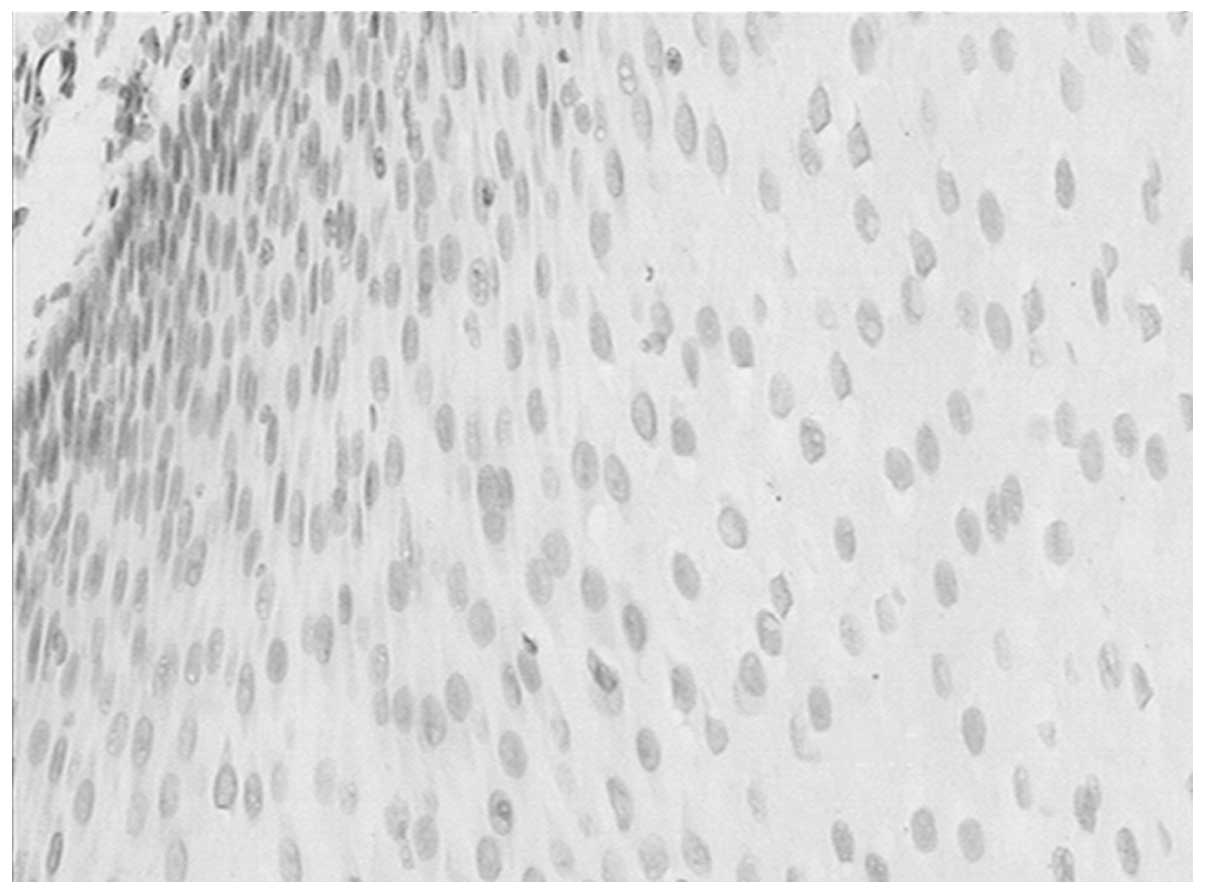

Correlation of CD146 expression and clinicopathological characteristics in esophageal squamous cell carcinoma

CD146, a cell adhesion molecule, is found in normal and tumor tissues. The level of its expression has been found to directly correlate with tumor progression and metastatic potential. The objective of this study was to investigate the expression of CD146 in esophageal squamous cell carcinoma (ESCC) and its correlation with clinicopathological parameters. Tumor specimens were collected from 63 patients with ESCC who underwent complete resection. We analyzed the CD146 expression levels in ESCC by immunohistochemistry. The expression of CD146 was detected and it was observed to correlate with clinicopathological parameters. Sixty‑three cases of normal squamous mucosa were included for comparison. CD146 expression was identified in 46.0% (29/63) of the ESCC samples, and no positive (weak to moderate or moderate to strong) expression was found in the normal squamous epithelium samples (χ2=27.248; P<0.0001). CD146 expression was associated with lymph node metastasis (χ2=5.117; P=0.024) and advanced clinical stage (χ2=4.661; P=0.031). CD146 expression was one of the significant predictors of survival (hazard ratio, 2.838; 95% confidence interval 1.102‑7.305). The overexpression of the CD146 gene was one of the important phenotypes and characteristics in ESCC carcinomatous change. We found that CD146 expression was associated with lymph node metastasis and advanced clinical stage, and was an indicator of poor prognosis in ESCC patients. CD146 may prove to be an important tumor marker for the individualized treatment for ESCC.

View Figures

Figure 1

Figure 2

Figure 3

Figure 4

Figure 5

Figure 6

Figure 7